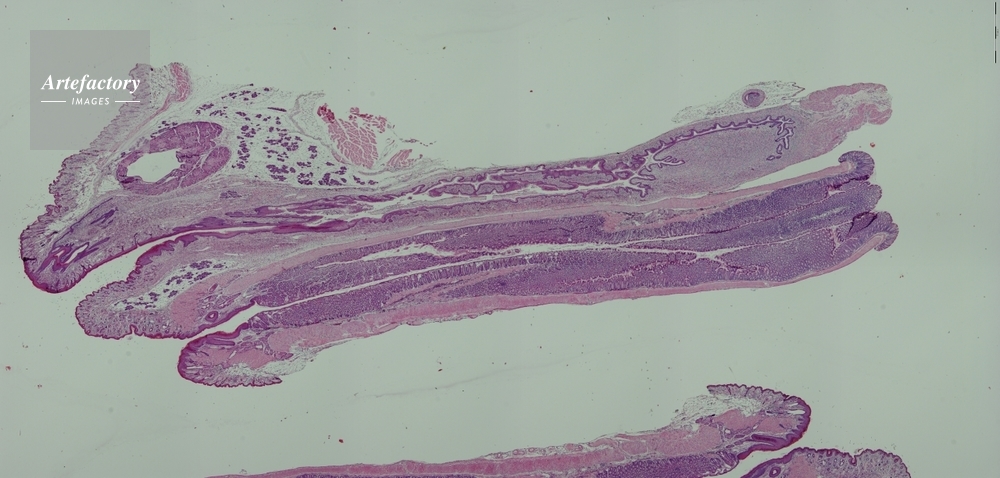

| 作品タイトル | マウス,膣、子宮、直腸 | モデルリリース | なし | |

| キャプション | 合成画像 | 制限事項 | ||

| ソース | ピクセル数 | 1280px × 612px | ||

| 撮影年月日 | 2007/7/2 | データサイズ | ||